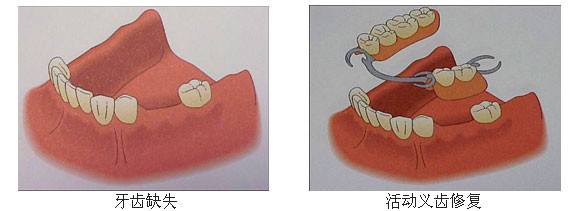

针对牙齿缺失,目前有三种方法可进行修复:活动义齿、烤瓷牙、种植牙。

活动义齿:利用剩余天然牙或粘膜做支撑,卡环或者基托固位,异物感强,容易脱落,适用于多颗牙缺失。